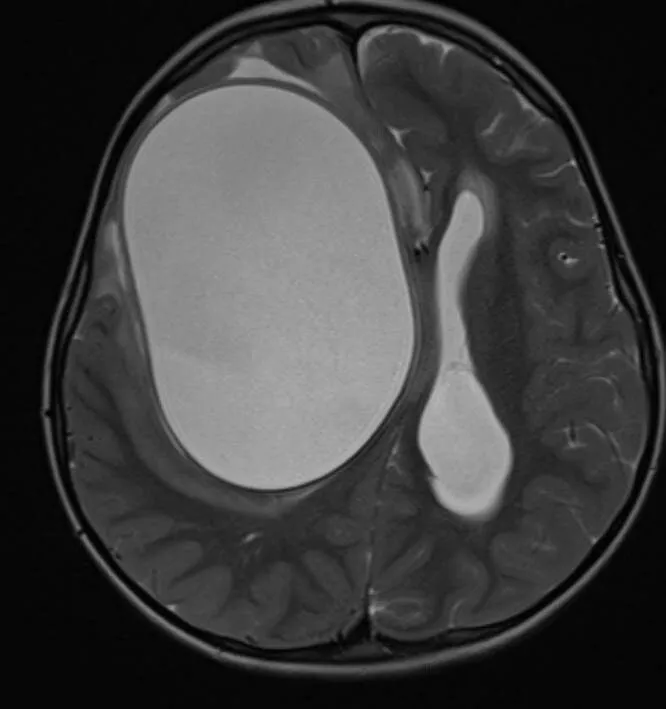

Новосибирск. 6 февраля. ИНТЕРФАКС - Хирурги Новосибирской областной клинической больницы удалили из головного мозга пятилетней девочки огромную кисту с паразитом внутри, сообщает пресс-служба Минздрава региона.

"Когда девочку госпитализировали, у нее не двигались левые рука и нога. Во время обследования врачи обнаружили два небольших образования в лёгких и огромное - больше 10 см диаметром - в головном мозге. Диагноз "эхинококкоз" подтвердился", - говорится в сообщении.

"Главная трудность такого вмешательства - капсулу нужно извлечь целиком, не нарушив целостность оболочки, толщина которой всего 1-2 миллиметра", - говорится в сообщении.

Содержимое паразитарной кисты очень токсично, в случае с головным мозгом нельзя откачать его через прокол, а после провести обработку специальными препаратами, как это делается, например, при операциях на печени.

Операция длилась несколько часов. Нейрохирурги сумели аккуратно высвободить и извлечь кисту.